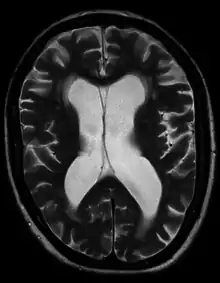

Hydrocephalus ex vacuo from vascular dementia as seen on MRI